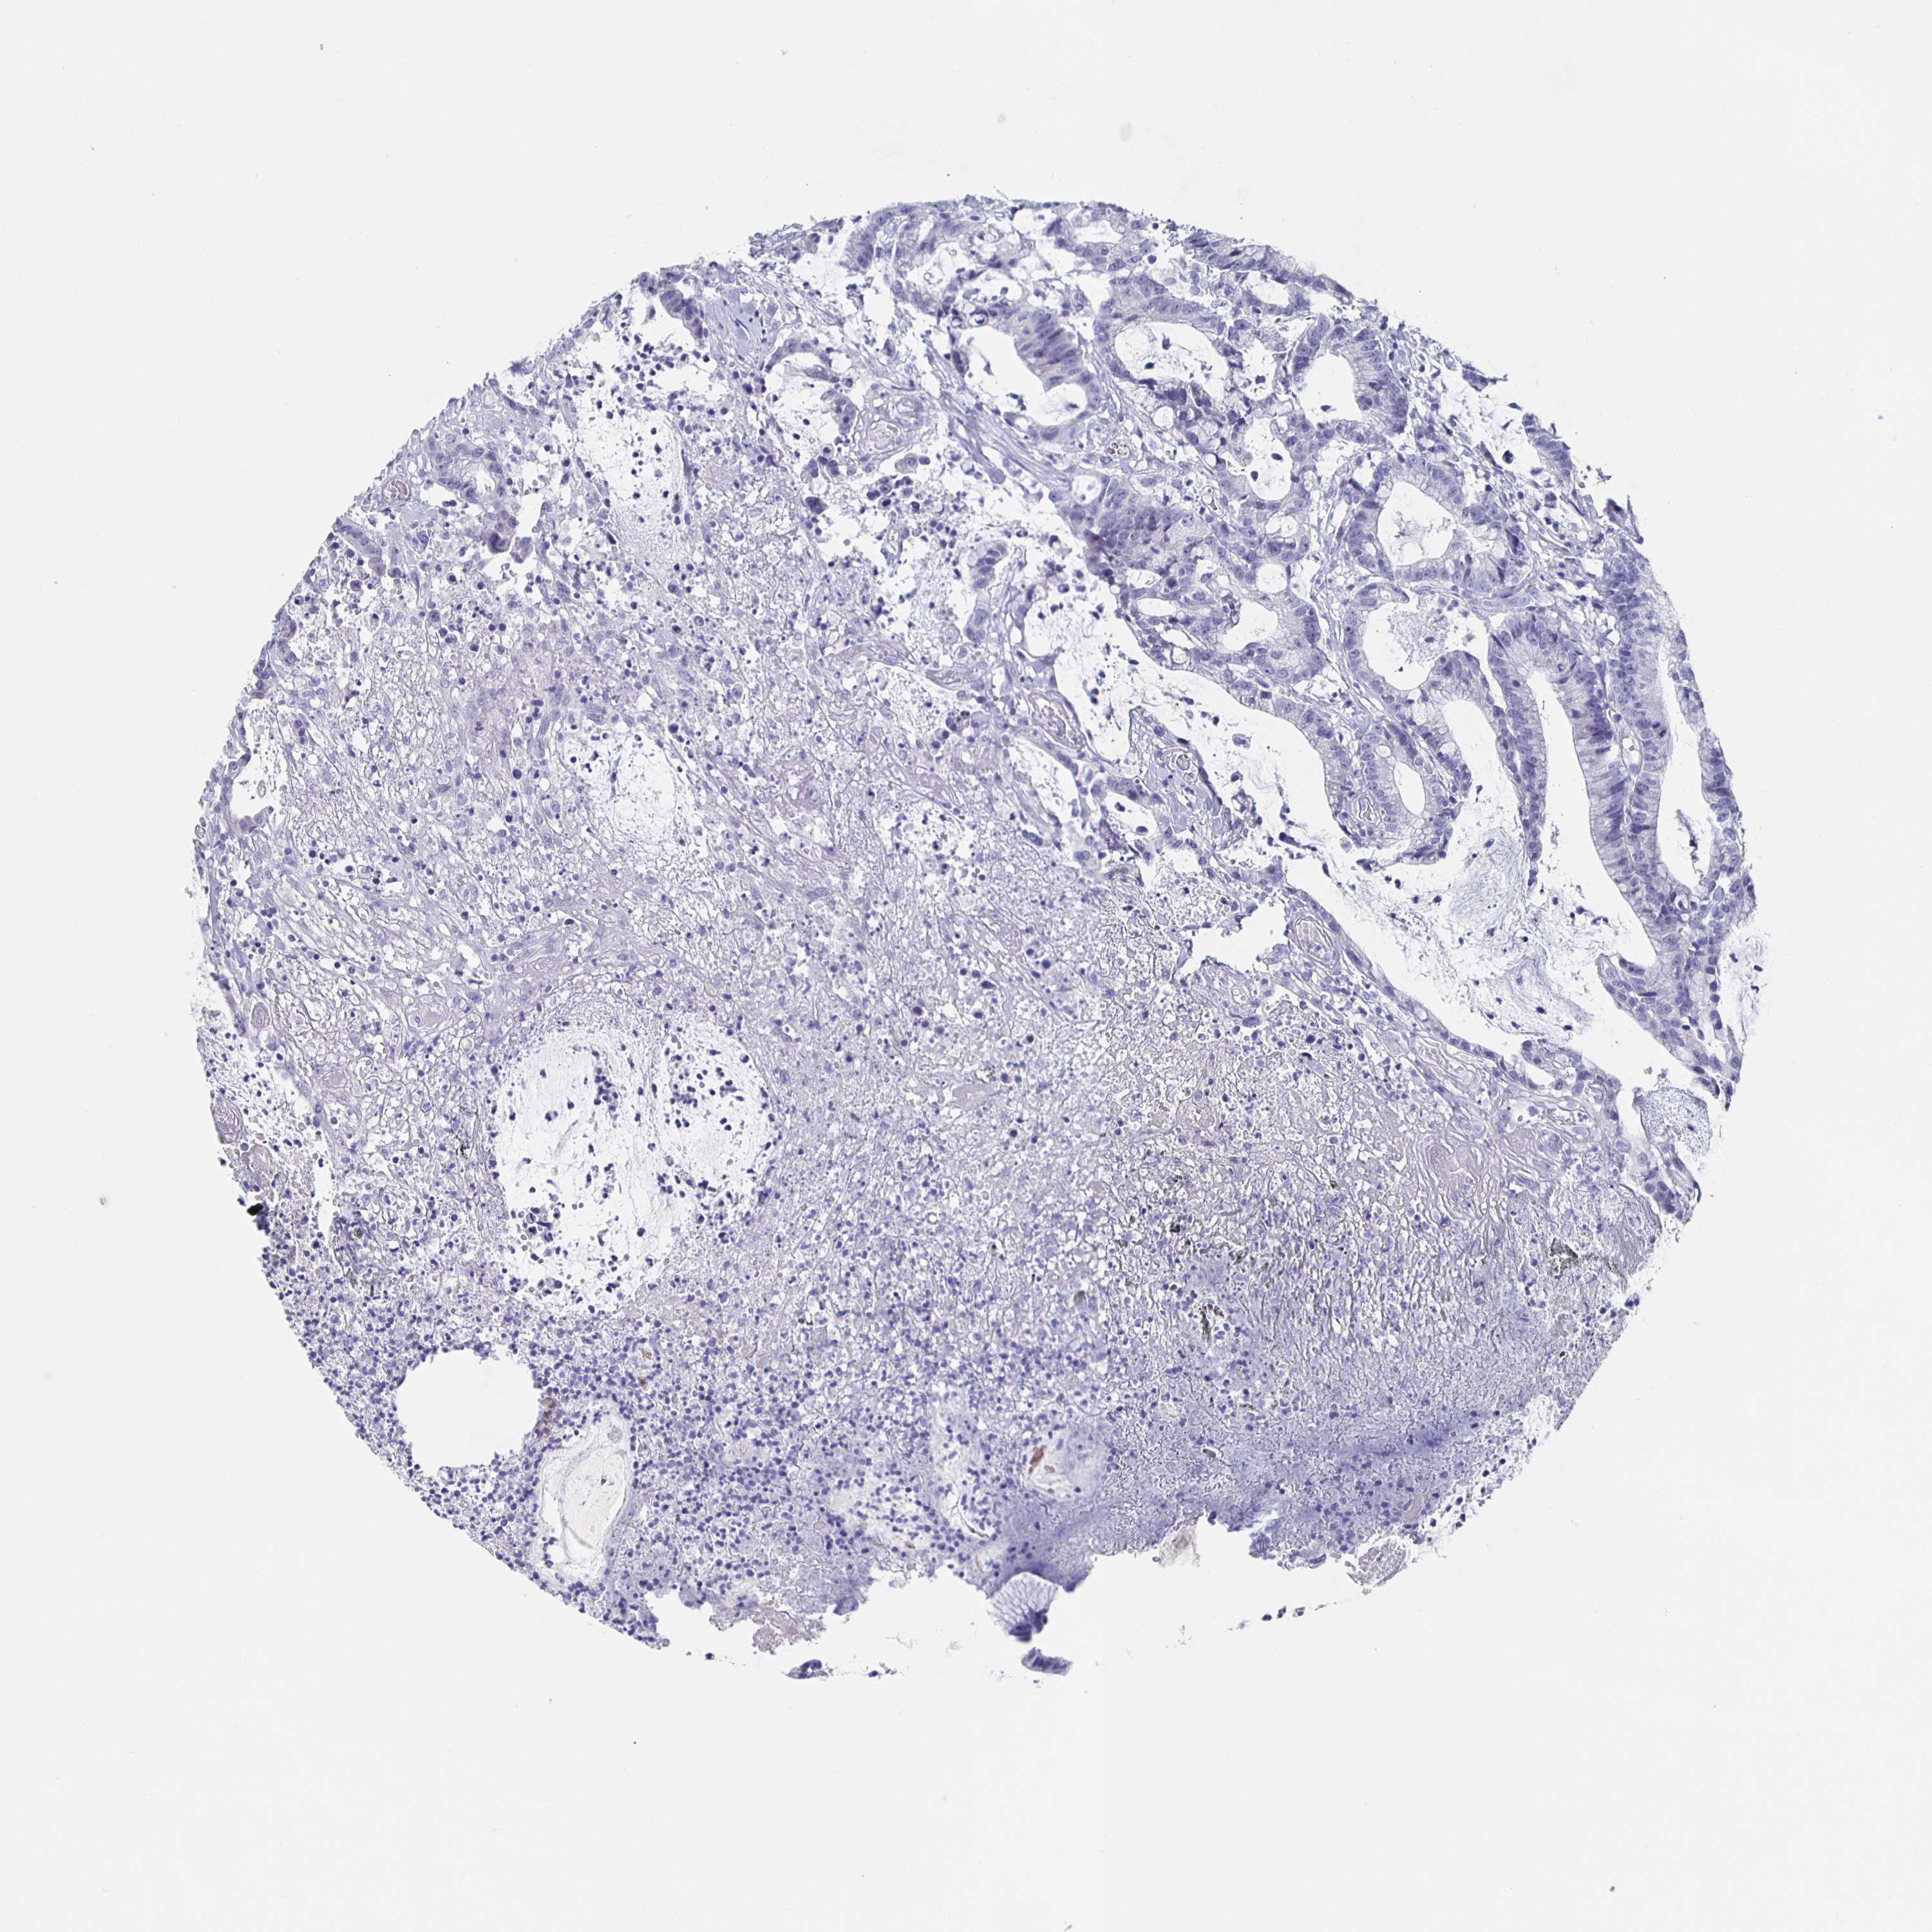

Colorectal cancer

Colon adenocarcinoma